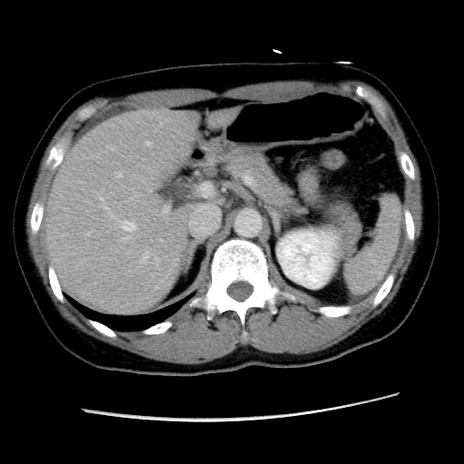

冠状断像

【症例】 50歳代女性

【主訴】 腹痛

【現病歴】前日生レバーを食べた。今朝に排便あり。 昼前に突然発症の腹痛を生じ、当院救急外来を受診した。

【身体所見】 意識清明、腹部:平坦、軟、下腹部やや左を中心に圧痛・反跳痛あり、筋性防御あり